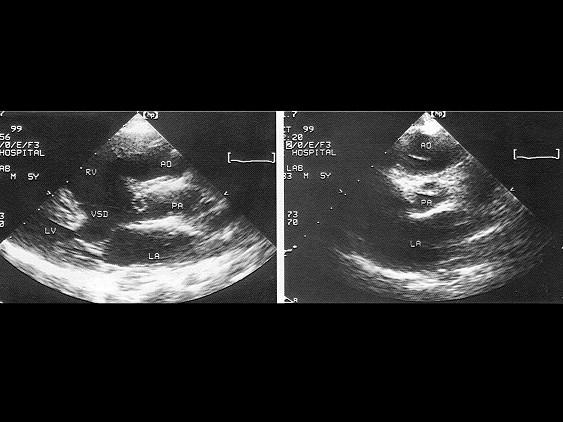

该病例最可能的诊断?(?)A.右室双出口并室间隔缺损B.主动脉骑跨C.室间隔缺损D.大动脉异位E.左室双出口

选项 A.右室双出口并室间隔缺损 B.主动脉骑跨 C.室间隔缺损 D.大动脉异位 E.左室双出口

答案 A